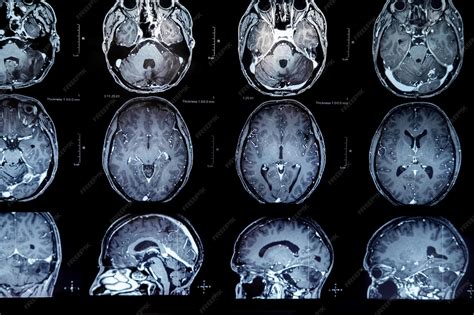

El diagnóstico de estas afecciones implica una combinación de análisis de sangre y pruebas de diagnóstico por la imagen.

- Pruebas de diagnóstico por la imagen: Se realizan tomografías computarizadas (TC) o resonancias magnéticas nucleares (RMN) de la cabeza para detectar tumores hipofisarios. Las radiografías del cráneo pueden mostrar engrosamiento óseo y de los senos paranasales, mientras que las radiografías de las manos pueden revelar engrosamiento óseo en las yemas de los dedos y el tejido circundante.